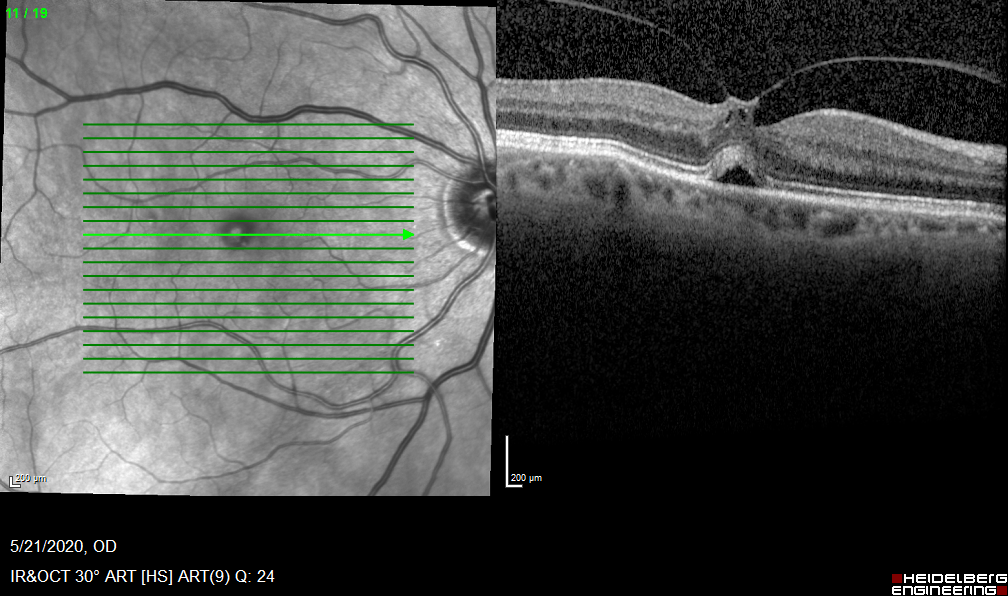

Case#2-PVH

Bilateral Macular holes. When to operate?